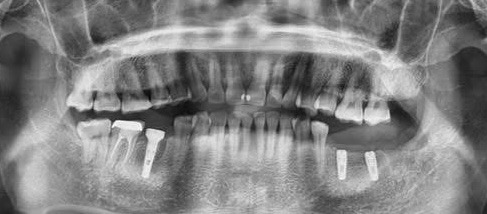

Reabilitare orala prin inserare a 3 implanturi dentare la nivelul cadranului II. In acelasi timp chirurgical s-a realizat aditie osoasa prin elevatia mucoasei sinusale in vederea asigurarii suportului osos necesar aplicarii implantului posterior.

Reabilitare implantara in cazul unor dinti restanti irecuperabili, cu mobilitate severa. Dupa extractia atraumatica a dintilor compromisi, tratamentul continua cu inserarea implanturilor dentare. In prealabil, in urma cu 6 luni s-a realizat aditie osoasa prin sinus lift extern la nivelul cadranului II, tehnica chirurgicala care ne-a permis inserarea implanturile posterioare.

Inserare 2 implanturi in cadranul III si un implant inserat post-extractional in cadranul IV